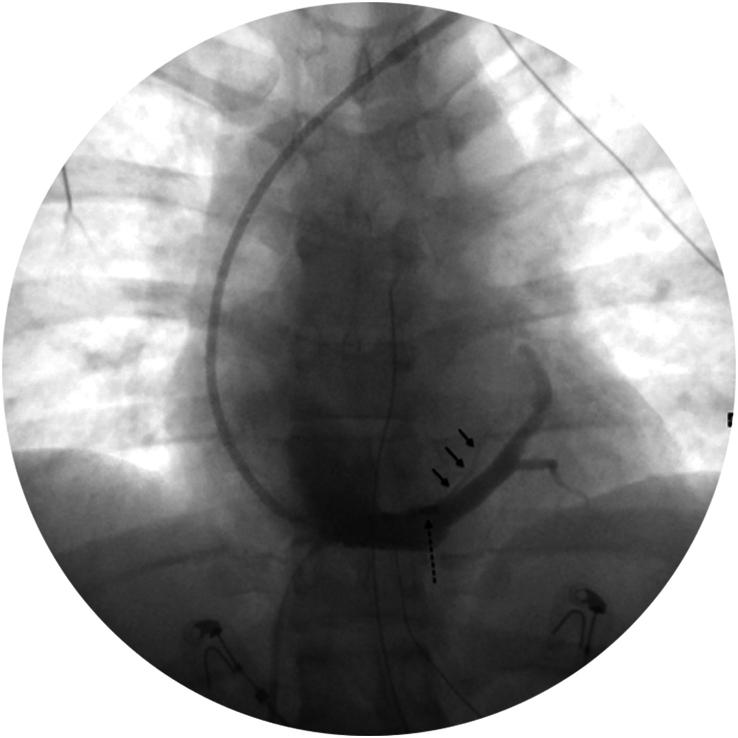

Atrial tachycardias (AT) originating from the Marshall bundle (MB) are rare and present significant challenges in diagnosis and management. The authors present the case of a 29-year-old male with recurrent AT successfully treated with a combined ethanol and radiofrequency ablation approach. This case highlights the effectiveness of this dual ablation strategy in resolving AT originating from the MB, contributing valuable insights into managing complex AT cases.

CASE PRESENTATION

A 29-year-old male with recurrent, symptomatic palpitations was initially suspected of orthodromic atrioventricular reentrant tachycardia, but an initial electrophysiological study (EPS) failed to induce arrhythmia. Subsequent spontaneous episodes led to a detailed EPS, revealing automatic AT originating presumably from an epicardial focus on the posterior wall of the left atrium (LA). Detailed mapping identified the earliest activation at the vein of Marshall (VoM) ostium within the coronary sinus (CS). Suspecting the involvement of MB structures, VoM ethanol ablation was performed. Complete arrhythmia elimination was achieved with radiofrequency ablation (RFA) at the VoM ostium within the CS, with no recurrence.

Most cases in the literature are associated with atrial fibrillation (AF) or AT within AF, typically involving re-entry mechanisms. The given case is unique as it presents a highly probable VoM origin of automatic AT with no concomitant AF. The VoM's anatomical and electrophysiological properties make it a potential source of refractory AT. In this case, ethanol ablation supplemented by targeted, limited RFA emerged as an effective strategy, highlighting the importance of comprehensive mapping and tailored ablation approaches in managing complex atrial arrhythmias.